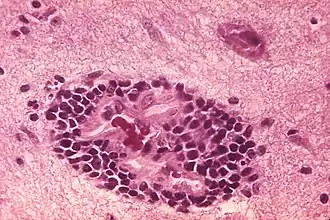

Verwekker

Het rabiësvirus is de typesoort van het genus Lyssavirus, in de familie Rhabdoviridae, orde Mononegavirales. Lyssavirussen hebben een helixvormige symmetrische structuur, met een lengte van ongeveer 180 nm en een doorsnede van ongeveer 75 nm.[4] Deze virussen hebben een envelop en zijn RNA virussen met een genoom van enkelstrengs RNA in negatieve (omgekeerde) richting (sense). Het genetische materiaal is verpakt als ribonucleoproteïnecomplex waarin RNA stevig is gebonden door het virale nucleoproteïne. Het RNA-genoom van het virus bevat vijf genen waarvan de volgorde zeer geconserveerd is: nucleoproteïne (N), fosfoproteïne (P), matrixproteïne (M), glycoproteïne (G) en het virale RNA-polymerase (L).[5]

Het virus is neurotroop (het richt zich op het zenuwweefsel): vanaf de plaats waar het virus het lichaam binnendringt, klimt het virus langs de zenuwbanen naar het centraal zenuwstelsel, en daarna naar andere organen.[7] De speekselklieren bevatten hoge concentraties van het virus, wat verdere overdracht via speeksel en/of een bijtwond mogelijk maakt. Dit wordt versterkt door het feit dat het virus de speekselproductie verhoogt en door de hydrofobie (afkeer van water en hevige krampen), alsmede de razernij veroorzaakt door de aantasting van de hersen- en zenuwcellen door het virus. Bij dieren verhoogt dit gedrag de kans op bijten en daarmee besmetting.